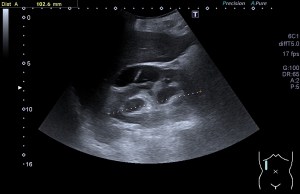

La radiografía revela aumento de las partes y se refrenda en la ecografía como puedes ver en la imagen aunque aún no hay afectación en el hueso en el caso que te presento hoy.

Ecografícamente y debido a su levedad, en el caso de hoy solo observamos cambios en las partes blandas de la cara lateral de la cabeza del quinto metatarsiano, este tejido se muestra heterogéneo, la cortical del hueso ligeramente prominente sin afectación de la misma.